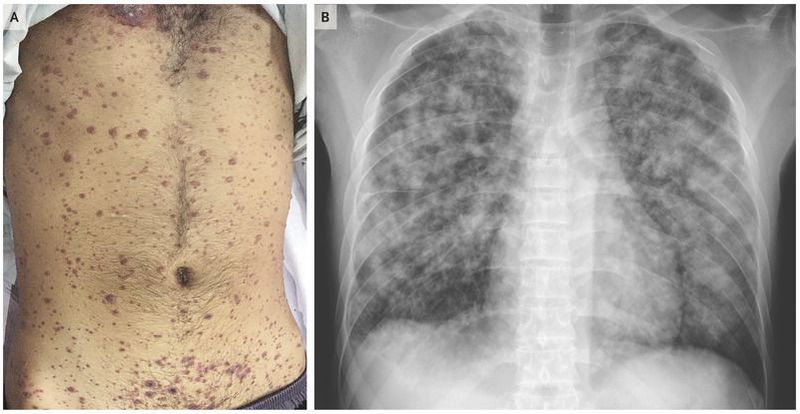

A 29-year-old man with a history of aplastic anemia who was being treated with cyclosporine presented to the emergency department with a 4-day history of fever, cough, and difficulty breathing at rest. One day before the onset of symptoms, a pruritic rash had developed on his face, trunk, and limbs. On physical examination, the pulse was 104 beats per minute, the blood pressure was 110/70 mm Hg, the respiratory rate was 36 breaths per minute, and the oxygen saturation was 90% while the patient was breathing high-flow oxygen. He had a diffuse rash at different stages of development, including papules, vesicles, pustules, and crusted vesicles (Panel A). Laboratory evaluation showed a platelet count of 33,000 per cubic millimeter (reference range, 150,000 to 400,000), an alanine aminotransferase level of 297 U per liter (reference range, 2 to 41), and an aspartate aminotransferase level of 281 U per liter (reference range, 2 to 40). A chest radiograph showed multiple nodules coalescing to form nodular consolidation and infiltrates in both lungs (Panel B). On the basis of his history of contact with a person who had chickenpox, along with the appearance of lesions and pulmonary symptoms in the context of immunosuppression, a clinical diagnosis of disseminated varicella infection was made. Despite treatment, which included intravenous acyclovir and mechanical ventilation with an acute respiratory distress syndrome protocol, the patient died 2 days after presentation.